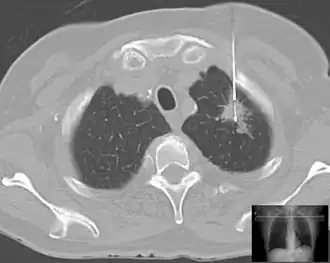

Lung biopsy in a case of suspected lung cancer under guidance of computed tomography.

When cancer is suspected, a variety of biopsy techniques can be applied. An excisional biopsy is an attempt to remove an entire lesion. When the specimen is evaluated, in addition to diagnosis, the amount of uninvolved tissue around the lesion, the surgical margin of the specimen is examined to see if the disease has spread beyond the area biopsied. "Clear margins" or "negative margins" means that no disease was found at the edges of the biopsy specimen. "Positive margins" means that disease was found, and a wider excision may be needed, depending on the diagnosis.